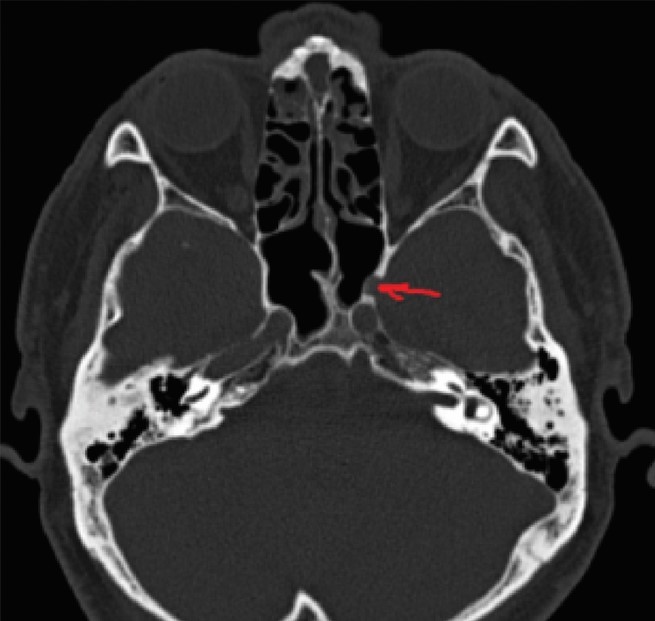

ВВЕДЕНИЕ В настоящее время в связи с распространением лучевых (МРТ, КТ) и визуальных (эндоскопия) методов диагностики наблюдается увеличение количества случаев изолированного сфеноидита [1, 2, 3]. Удельный вес изолированного сфеноидита в общей структуре заболеваний околоносовых пазух (ОНП), по данным литературы, составляет не более 5% [4, 5, 6]. Однако абсолютные цифры с учетом огромного количества случаев воспалительной патологии ОНП могут быть весьма значительными. В структуре синуситов все больше резистентных (устойчивых к лечению) форм, в том числе грибковых [7]. Данные о распространенности патологии весьма скудные, в структуре статистической отчетности стационаров и поликлиник сфеноидит как самостоятельная нозологическая форма отражается крайне редко. В то же время относительно невысокая распространенность нередко обусловливает пассивную позицию специалистов при дифференциальной диагностике поражений клиновидной пазухи (КП). Основное место в дифференциальной диагностике у данной группы пациентов занимают компьютерная томография (КТ) и магнитно-резонансная томография (МРТ). Однако трактовка результатов исследований не всегда однозначна и может приводить как к гипердиагностике, так и, наоборот, к гиподиагностике сфеноидита, выражающейся в недооценке данных лучевой диагностики и обьективной картины и нередко приводящей к развитию хронических и осложненных форм. Пациенты направляются к лор-врачу только после длительного, безуспешного лечения у специалистов смежных специальностей, что влечет высокий уровень гиподиагностики сфеноидита и наличие осложненных форм [8]. Дифференциальная диагностика патологического процесса в пазухе на дооперационном этапе чрезвычайно важна, поскольку необдуманное вмешательство может вызвать тяжелые и даже фатальные осложнения [9, 10]. От 5% до 30% всех изолированных поражений клиновидной пазухи составляют пациенты с неинвазивной грибковой формой [11, 12]. Для хронического сфеноидита характерно латентное (скрытое) течение, которое не всегда диагностируется на ранних стадиях [13, 14]. По данным ряда исследователей, частота патологических находок в клиновидной пазухе при аутопсии лиц, прижизненный диагноз «сфеноидит» у которых не был установлен, составляет от 10% до 68% [15, 16]. Очень важно изучение вопросов ремоделирования в клиновидной пазухе, в том числе явлений остеита при грибковых формах [17]. Осложненное течение изолированного сфеноиди-та - нередкое явление, при этом основным фактором развития осложнений является несвоевременная диагностика. Наиболее часто встречаются осложнения, связанные с вовлечением в патологический процесс глазодвигательных нервов, в особенности VI пары - n. abducens [4, 9, 16]. В литературе можно встретить наблюдения инвазивных, генерализованных форм грибкового сфеноидита с быстрым развитием офтальмологических, интракраниальных и системных (септических) осложнений [7, 12, 14]. Тактика лечения при изолированных поражениях клиновидной пазухи, по данным литературы, различная. Часть авторов считает наличие изолированного сфеноидита, особенно грибковых форм, мукоцеле, абсолютным показанием к операции. Другие авторы при отсутствии осложнений начинают с консервативной терапии [1, 3, 11, 12]. Задачей хирургического лечения у таких пациентов является не только купирование воспалительного процесса, но и создание условий для адекватной вентиляции пазух и предотвращения возможного рецидива. В то же время вопросы дифференцированного подхода к хирургическому лечению недостаточно освещены в научной литературе и носят преимущественно описательный характер. ш ЦЕЛЬ Провести анализ случаев изолированного поражения клиновидной пазух и выявить основные особенности и ошибки при дифференциальной диагностике на догоспитальном этапе. ш МАТЕРИАЛ И МЕТОДЫ В работе приведены данные о лечении 58 пациентов с изолированным поражением клиновидной пазухи, которые находились на стационарном лечении в ГБУЗ НОКБ им. Н.А. Семашко (кафедра болезней уха, горла и носа ФГБОУ ВО «ПИМУ» Минздрава РФ) в период 2015-2018 гг. Возраст пациентов - от 18 до 68 лет. Средний возраст пациентов с изолированным сфеноидитом составил 43 года, среди них превалировали женщины до 35 лет. Гендерное распределение было следующее: мужчины - 21 (30,7 %), женщины - 37 (69,3%). Давность заболевания составила 26±19 дней. Всего в клинике в данный период наблюдались 118 пациентов с различными формами поражения клиновидной пазухи, у 60 пациентов поражение КП наблюдалось как проявление хронического риносинусита (с полипами и без), то есть имело место сочетанное поражение нескольких или всех околоносовых пазух, и данные наблюдения не были включены в исследование. Критерии включения в исследование: рентгенологические (КТ, МРТ) признаки патологического процесса в клиновидной пазухе, специфическая и неспецифическая симптоматика, латентное течение сфеноидита, отсутствие патологического процесса в других околоносовых пазухах. Критерии исключения: сочетанное поражение других групп околоносовых пазух, нозокомиальный сфенои-дит. Такие состояния, как искривление носовой перегородки, вазомоторный/аллергический ринит, гипертрофия носовых раковин, mnchabullosa средних носовых раковин критериями исключения не являлись. Пациенты с впервые установленным диагнозом составили 85% от общего числа, 15% наблюдений - рецидивные формы заболевания, в том числе 5 пациентов были после ранее проведенного оперативного вмешательства (таблица 1). Морфологическая форма Количество наблюдений Полипозный процесс 15 (25,8%) Киста 18 (31%) Мукоцеле 5 (8,6%) Грибковый сфеноидит 12 (20,6%) Инвазивный грибковый сфеноидит 2 (3,4%) Менингоцеле 4 (6,8%) Новообразование 2 (3,4%) Таблица1. Распределение по виду патологического процесса Table 1. Distribution by the type of pathological process При поступлении в стационар проведено обследование пациентов в следующем объеме: клинические анализы, консультации смежных специалистов - невролога, нейрохирурга, офтальмолога (в зависимости от клинических проявлений). Всем пациентам проводилась предоперационная эндориноскопия. При подготовке к оперативному лечению оценивалось наличие у пациента сопутствующих заболеваний, течение которых проявляется симптоматикой со стороны ОНП и может в значительной степени оказывать влияние на течение патологического процесса в полости носа и ОНП: бронхиальная астма, аспириновая триада, персистирующий или интермиттирующий аллергический ринит, а также комбинация данных заболеваний. ш ОБСУЖДЕНИЕ И РЕЗУЛЬТАТЫ В большинстве случаев причиной обращения за помощью был цефалгический синдром. Все пациенты с болевым синдромом первоначально проходили обследование у невролога либо терапевта, им выполнялось МРТ-исследование на догоспитальном этапе. В данной группе пациентов (n=21, 36,2%) 9 человек были направлены к оториноларингологу сразу после получения данных МРТ. 12 пациентов проходили дальнейшее консервативное лечение у невролога либо не получали никакого лечения, несмотря на очевидные данные МРТ-исследования. После МРТ-исследования уточняющее КТ-исследование было назначено только 3 пациентам. Остальные пациенты были направлены в стационар с результатами МРТ. Таким образом, в рамках нашего исследования можно говорить о превалировании МРТ-диагностики в догоспитальном обследовании и игнорировании специалистами КТ-исследования. Симптоматическая картина у исследуемых пациентов весьма вариабельна: от латентных бессимптомных форм до тяжелых цефалгических и офтальмологических проявлений. Мы наблюдали определенную взаимосвязь между симптоматическими проявлениями и морфологической формой заболевания (таблица 2). В целом манифестирующая ринологическая симптоматика наблюдалась не более чем в трети наблюдений. В остальных ситуациях мы наблюдали либо неспецифическую симптоматику (цефалгические и/ или офтальмоплегические проявления), либо бессимптомное течение. Латентные формы поражений КП, когда патологический процесс выявлен случайно при МРТ/КТ-обследовании по другим причинам, составили около 20% от всех наблюдений. Чаще всего это были поражения в виде кисты клиновидной пазухи и мукоцеле (рисунок 1), реже бессимптомное течение наблюдалось при грибковой форме поражения и менингоцеле (рисунки 2, 3). Хирургическое лечение. Всем пациентам проводилось хирургическое лечение, после тщательного анализа КТ-томограмм для уточнения варианта строения клиновидной пазухи и наличия анатомических вариантов строения (клетки Оноди, дигисценции канала внутренней сонной артерии, зрительного нерва и т.д.) (рисунки 4а, 4б). Все оперативные вмешательства выполнялись под общим обезболиванием. Применялись следующие доступы: трансназальный, расширенный трансназальный, трансэтмоидальный, доступ по методике Bolger Box, транскрыловидный (в одном случае) (таблица 3, фото 5, 6). Расширенный доступ (Wormald PJ. 2005, Palmer J.N. 2013) в отличие от традиционного с механическим расширением естественного соустья подразумевает выкраивание короткого (5-10 мм) назосептального лоскута Морфологическая форма Клинические симптомы Головная боль Постназальный затек Голово кружение Назальная обструкция Глазничные симптомы Полипозный процесс/ полипозно-гнойный + +++ - ++ - Киста - - - + - Мукоцеле ++ + - + - Грибковый сфеноидит ++ ++ + + + Инвазивный грибковый сфеноидит +++ ++ + + +++ Менингоцеле + + + - - Новообразование ++ + + - +++ «+» - степень выраженности симптома от + до +++. «-» - отсутствие симптома. Таблица 2. Симптоматические проявления Table 2. The symptomatic manifestation Рисунок 1. Мукоцеле клиновидной пазухи. Figure 1. Mucocele of the sphenoid sinus. Рисунок 2. Грибковый сфеноидит. 2.1 КТ (аксиальный срез); 2.2 Соустье обтурировано полипом. Трансназальный доступ; 2.3 - грибковые массы в пазухе. Figure 2. Fungal sphenoiditis. 2.1 CT (axial cross-section); 2.2 Anastomosis is obturated by a polyp. Transnasal access; 2.3 - fungal masses in the sinus. Рисунок 3. КТ (фронтальный срез). Остеит стенок клиновидной пазухи при грибковом синусите. Figure 3. CT (front section). Osteitis of the walls of the sphenoid sinus in fungal sinusitis. Рисунок 4а. Дигисценция канала внутренней сонной артерии. КТ-исследование. Figure 4a. Dehiscence of the internal carotid artery channel. CT study Рисунок 4б. Дигисценция канала внутренней сонной артерии. Эндоскопическая картина. Figure 4b. Dehiscence of the internal carotid artery channel. Endoscopic image. Таблица 3. Виды хирургических вмешательств Table 3. Types of surgical interventions слизистои ниже и медиальнее соустья пазухи на ножке с питанием от заднеИ септальноИ ветви крылонебной артерии с широким обнажением и резекцией передней стенки пазухи. При этом соустье мы расширяли при помощи бора. Данный способ упрощает задачу в том случае, если естественное соустье не визуализируется и технически не доступно и/или есть необходимость широкого открытия пазухи. Лоскут на питающей ножке используется для закрытия широкого костного дефекта, что способствует его дальнейшей эпите-лизации и минимизирует развитие в последующем остеита. Исследования ряда авторов свидетельствуют о том, что трансэтмоидальный и трансназальный доступ могут с одинаковым успехом применяться при Рисунок 5. 5a - грибковое тело латерального кармана клиновидной пазухи (КТ, аксиальный срез); 5b - расширенный трансназальный доступ (700 эндоскоп); 5c - КТ через 6 мес. после операции. Figure 5. 5a - fungal ball in the lateral “pocket" of the sphenoid sinus (CT, axial section); 5b - extended transnasal access (700 endoscope); 5c - CT in 6 months after operation. Рисунок 6. Менингоцеле клиновидной пазухи. 6а - МРТ (фронтальный срез); 6b - расширенный трансназальный доступ. Пластика ликворного дефекта после удаления менингоцеле (материал - жир). Figure 6. Meningocele of the sphenoid sinus. 6a - MRI (frontal section); 6b - extended transnasal access. Plasty of the liquor defect after the meningocele removal (the material - fat). Рисунок 7. Соустье через 1 год после расширенного доступа. Figure 7. Anastomosis 1 year after expanded access. Рисунок 8. Соустье через 3 года после расширенного трансназального доступа. Рисунок 9. Рецидив полипозно-гнойного сфеноидита через 6 месяцев после операции. причиной рецидива патологического процесса и потребовал проведения ревизионного вмешательства. В одном случае у пациента, которому ранее выполнена сфенотомия по поводу хронического сфеноидита, но не была вскрыта (распознана) клетка Оноди, в которой локализовалось грибковое воспаление, также потребовалась повторная операция. Figure 9. Recurrence of polypous-purulent sphenoiditis in 6 months after surgery. Figure 8. Anastomosis 3 years after expanded access. изолированном поражении пазухи. Трансназальный доступ более безопасен, чем трансэтмоидальный, и является методом выбора при изолированном поражении пазухи при условии, что патологический процесс в пазухе не требует широкой ревизии и/или создания достаточного по объему сообщения в тех ситуациях, когда велик риск рецидива. Осложнений в послеоперационном периоде не наблюдалось. На 5-7 сутки всем пациентам выполнялась эндориноскопия. В срок от 2 до 3 месяцев 11 пациентам выполнено контрольное КТ. Остальные пациенты (из отдаленных районов) не проходили контрольного осмотра. При выполнении расширенного доступа удалось добиться формирования стойкого, эпителизи-рованного соустья во всех случаях (рисунки 7, 8). При полипозно-гнойных формах сфеноидита наиболее часто наблюдались рецидивы заболевания, однако здесь требовалась только противовоспалительная терапия, в том числе орошение пазухи через сформированное соустье (рисунок 9). Частота развития спаечного процесса после вмешательств составила около 20%, при этом только в 3 наблюдениях рубцово-спаечный процесс явился ш ВЫВОДЫ Изолированный сфенои-дит в структуре пациентов, которым проводилось эндохирургическое лечение при патологии ОНП, составил 3% (около 30% от общего числа сфеноидитов). В стационаре пациенты с точно установленным диагнозом «изолированный сфеноидит» на догоспитальном этапе составили не более 12% от общего числа, что связано как с гиподиагностикой, пассивной позицией в отношении патологии клиновидной пазухи у врачей амбулаторного звена, так и с тактическими ошибками. Отмечено превалирование МРТ-диагностики в догоспитальном обследовании и игнорирование специалистами КТ-исследования. Основной метод лечения изолированного сфеноидита - хирургический. Наиболее часто применялся расширенный трансназальный доступ. Необходимо сочетание с медикаментозным лечением в послеоперационном периоде. Требуются дальнейшие исследования с целью изучения особенности/безопасности и клинической эффективности различных эндохирургических доступов. W Конфликт интересов: все авторы заявляют об отсутствии конфликта интересов, требующего раскрытия в данной статье.Об авторах